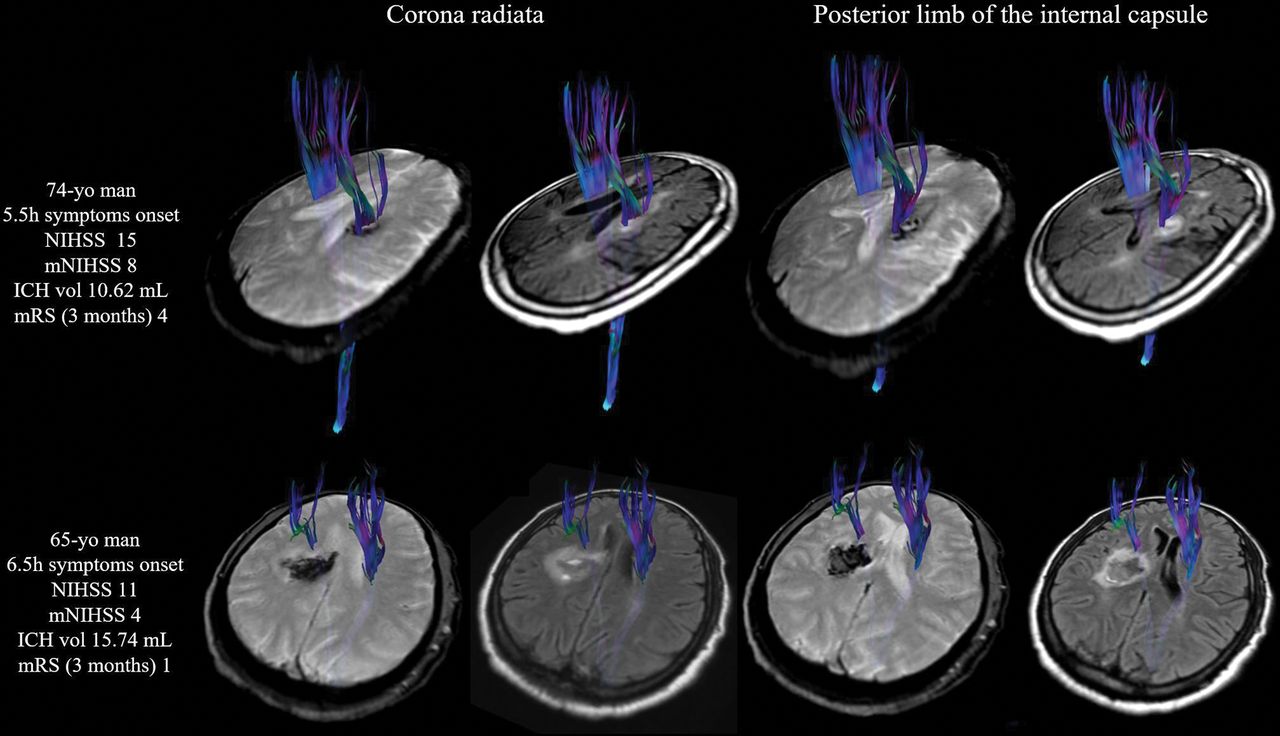

Assessing corticospinal tract involvement with diffusion tensor tractography superimposed on gradient recalled echo and FLAIR images. In the upper row, the corticospinal tract was affected by ICH (passes through it) at the level of the corona radiata and posterior limb of the internal capsule. Note that in lower row, the corticospinal tract was displaced slightly forward but preserved around the intracerebral hematoma. Vol indicates volume.

Analysis of Variables Associated with Clinical Outcome

In the 13 patients with poor motor outcome at 3 months, NIHSS and mNIHSS scores were higher at admission and at 72 hours than for patients with a good motor outcome (On-line Table 1). Patients with poor motor outcome had higher ICH volume at admission (10.45 mL; IQR = 5.07–15.74 mL versus 22.74 mL; IQR = 10.3–30; P = .034) (On-line Table 1). At admission, ICH involved the CST in 11 (84.61%) patients with poor motor outcome and in 13 (43.33%) patients with good motor outcome (P = .016); ICH involved the PLIC in 9 (69.23%) patients with poor motor outcome (P = .001). Poor motor outcome at 3 months correlated with functional outcome (mRS) at 3 months (P < .001). Patients with poor functional outcome had higher NIHSS and mNIHSS scores at admission and follow-up than patients with good outcome, as well as higher volumes of ICH (On-line Table 2). Poor functional outcome was also associated with CST affected by ICH. CST affected by PHE and quantitative DTI measures did not influence a patient's outcome (On-line Tables 1 and 2).